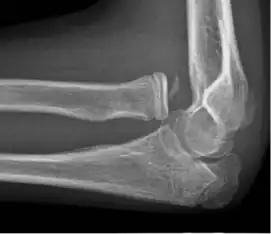

- Elbow

![X-ray of ventral dislocation of the radial head. There is calcification of annular ligament, which can be seen as early as 2 weeks after injury.[52]](./_assets_/X-ray_of_ventral_dislocation_of_the_radial_head_with_calcification_of_annular_ligament.jpg)